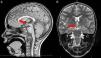

Brain MRI showed a HH 1.3cm in size located between the mamillary bodies (Fig. 2). The screening for precocious puberty was negative.